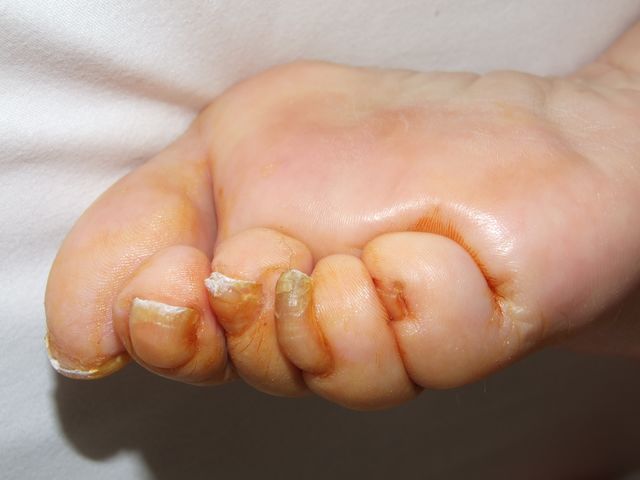

Malposición dedos.